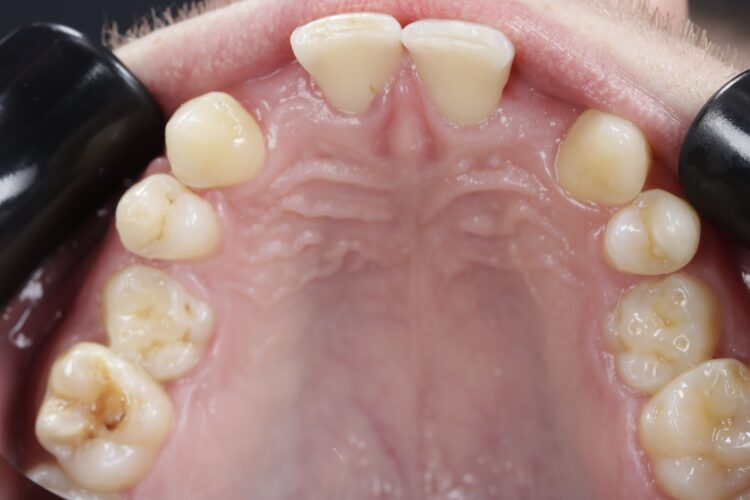

Case outcome

Both the patient and I were very happy with the outcome in this case. Given the patient’s reluctance towards excessive treatment, he was not willing to undergo any further procedures such as composite edge bonding or veneers, which could have enhanced the aesthetic result. However, he was more than satisfied with the replacement of his missing lateral incisors, and while he understands that more implants will be needed in the future when the remaining deciduous teeth are lost, he was happy to postpone that treatment for now.

This case presentation shows a real-life result of the kind of treatment we deliver every day in our clinic. It also demonstrates how a guided workflow allows us to place implants exactly as planned, making the process easier and more efficient.